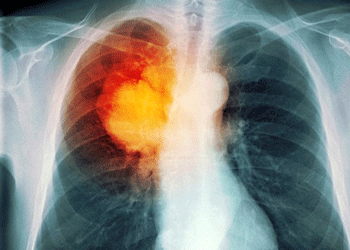

As long as the mineral remains outside the body, uranium poses little health hazards. However, if uranium is inhaled or ingested, its radioactivity and toxicity pose increased risks of lung cancer as well as cancer of bones, stomach, soft tissue and blood. It may also cause damage to internal organs notably kidneys alongside affecting the reproductive system, leading to birth defects in future generations.